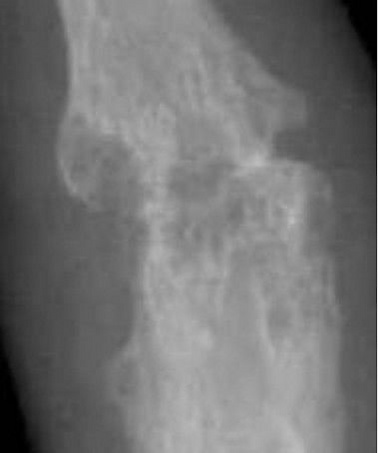

Такие методы визуализации, как рентгенография, магнитно-резонансная томография и компьютерная томография, позволяют визуализировать суставы и выявить любые структурные аномалии, воспаления или повреждения.